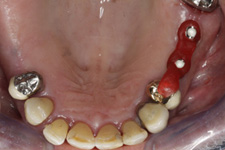

Během let může postupnou ztrátou zubů zůstat v ústech omezený počet zubů, které umožňují držení zubních náhrad.

V důsledku přetížení zbylých zubů např. houpavými pohyb snímacích náhrad dochází k uvolnění těchto zubů a držení můstků a protéz je tak velmi těžké. V těchto případech můžeme pomocí implantátů zvýšit počet pilířů a tím zabránit přetěžování a ztrátě zbylých zubů